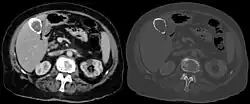

Eine Porzellangallenblase ist eine Erkrankung der Gallenblase, bei der es zu einer Verhärtung der Wand kommt. Die Verhärtung wird durch fibröse Bindegewebsfasern (Narbengewebe) und Kalk bewirkt. Letzterer gibt der Porzellangallenblase ihren Namen. Sie sieht weißlich aus und fühlt sich hart an wie Porzellan. Im Ultraschall zeigt sich die Gallenblasenwand verdickt und verdichtet, im Röntgenbild ist ihre Kontur zu erkennen.